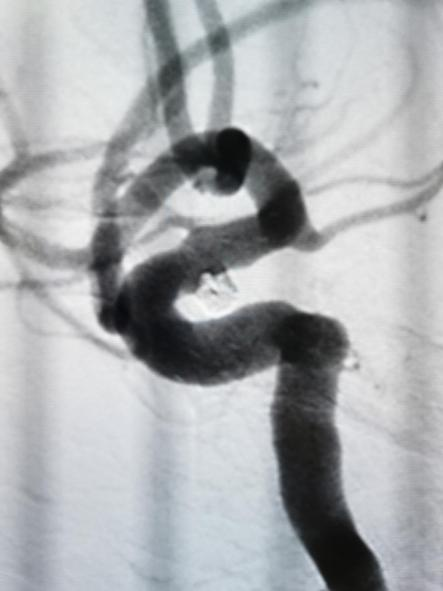

4.入路血管损伤

术中栓塞:

此患者动脉瘤栓塞术后一般情况良好,自诉眼睑下垂明显改善,临床随访中。